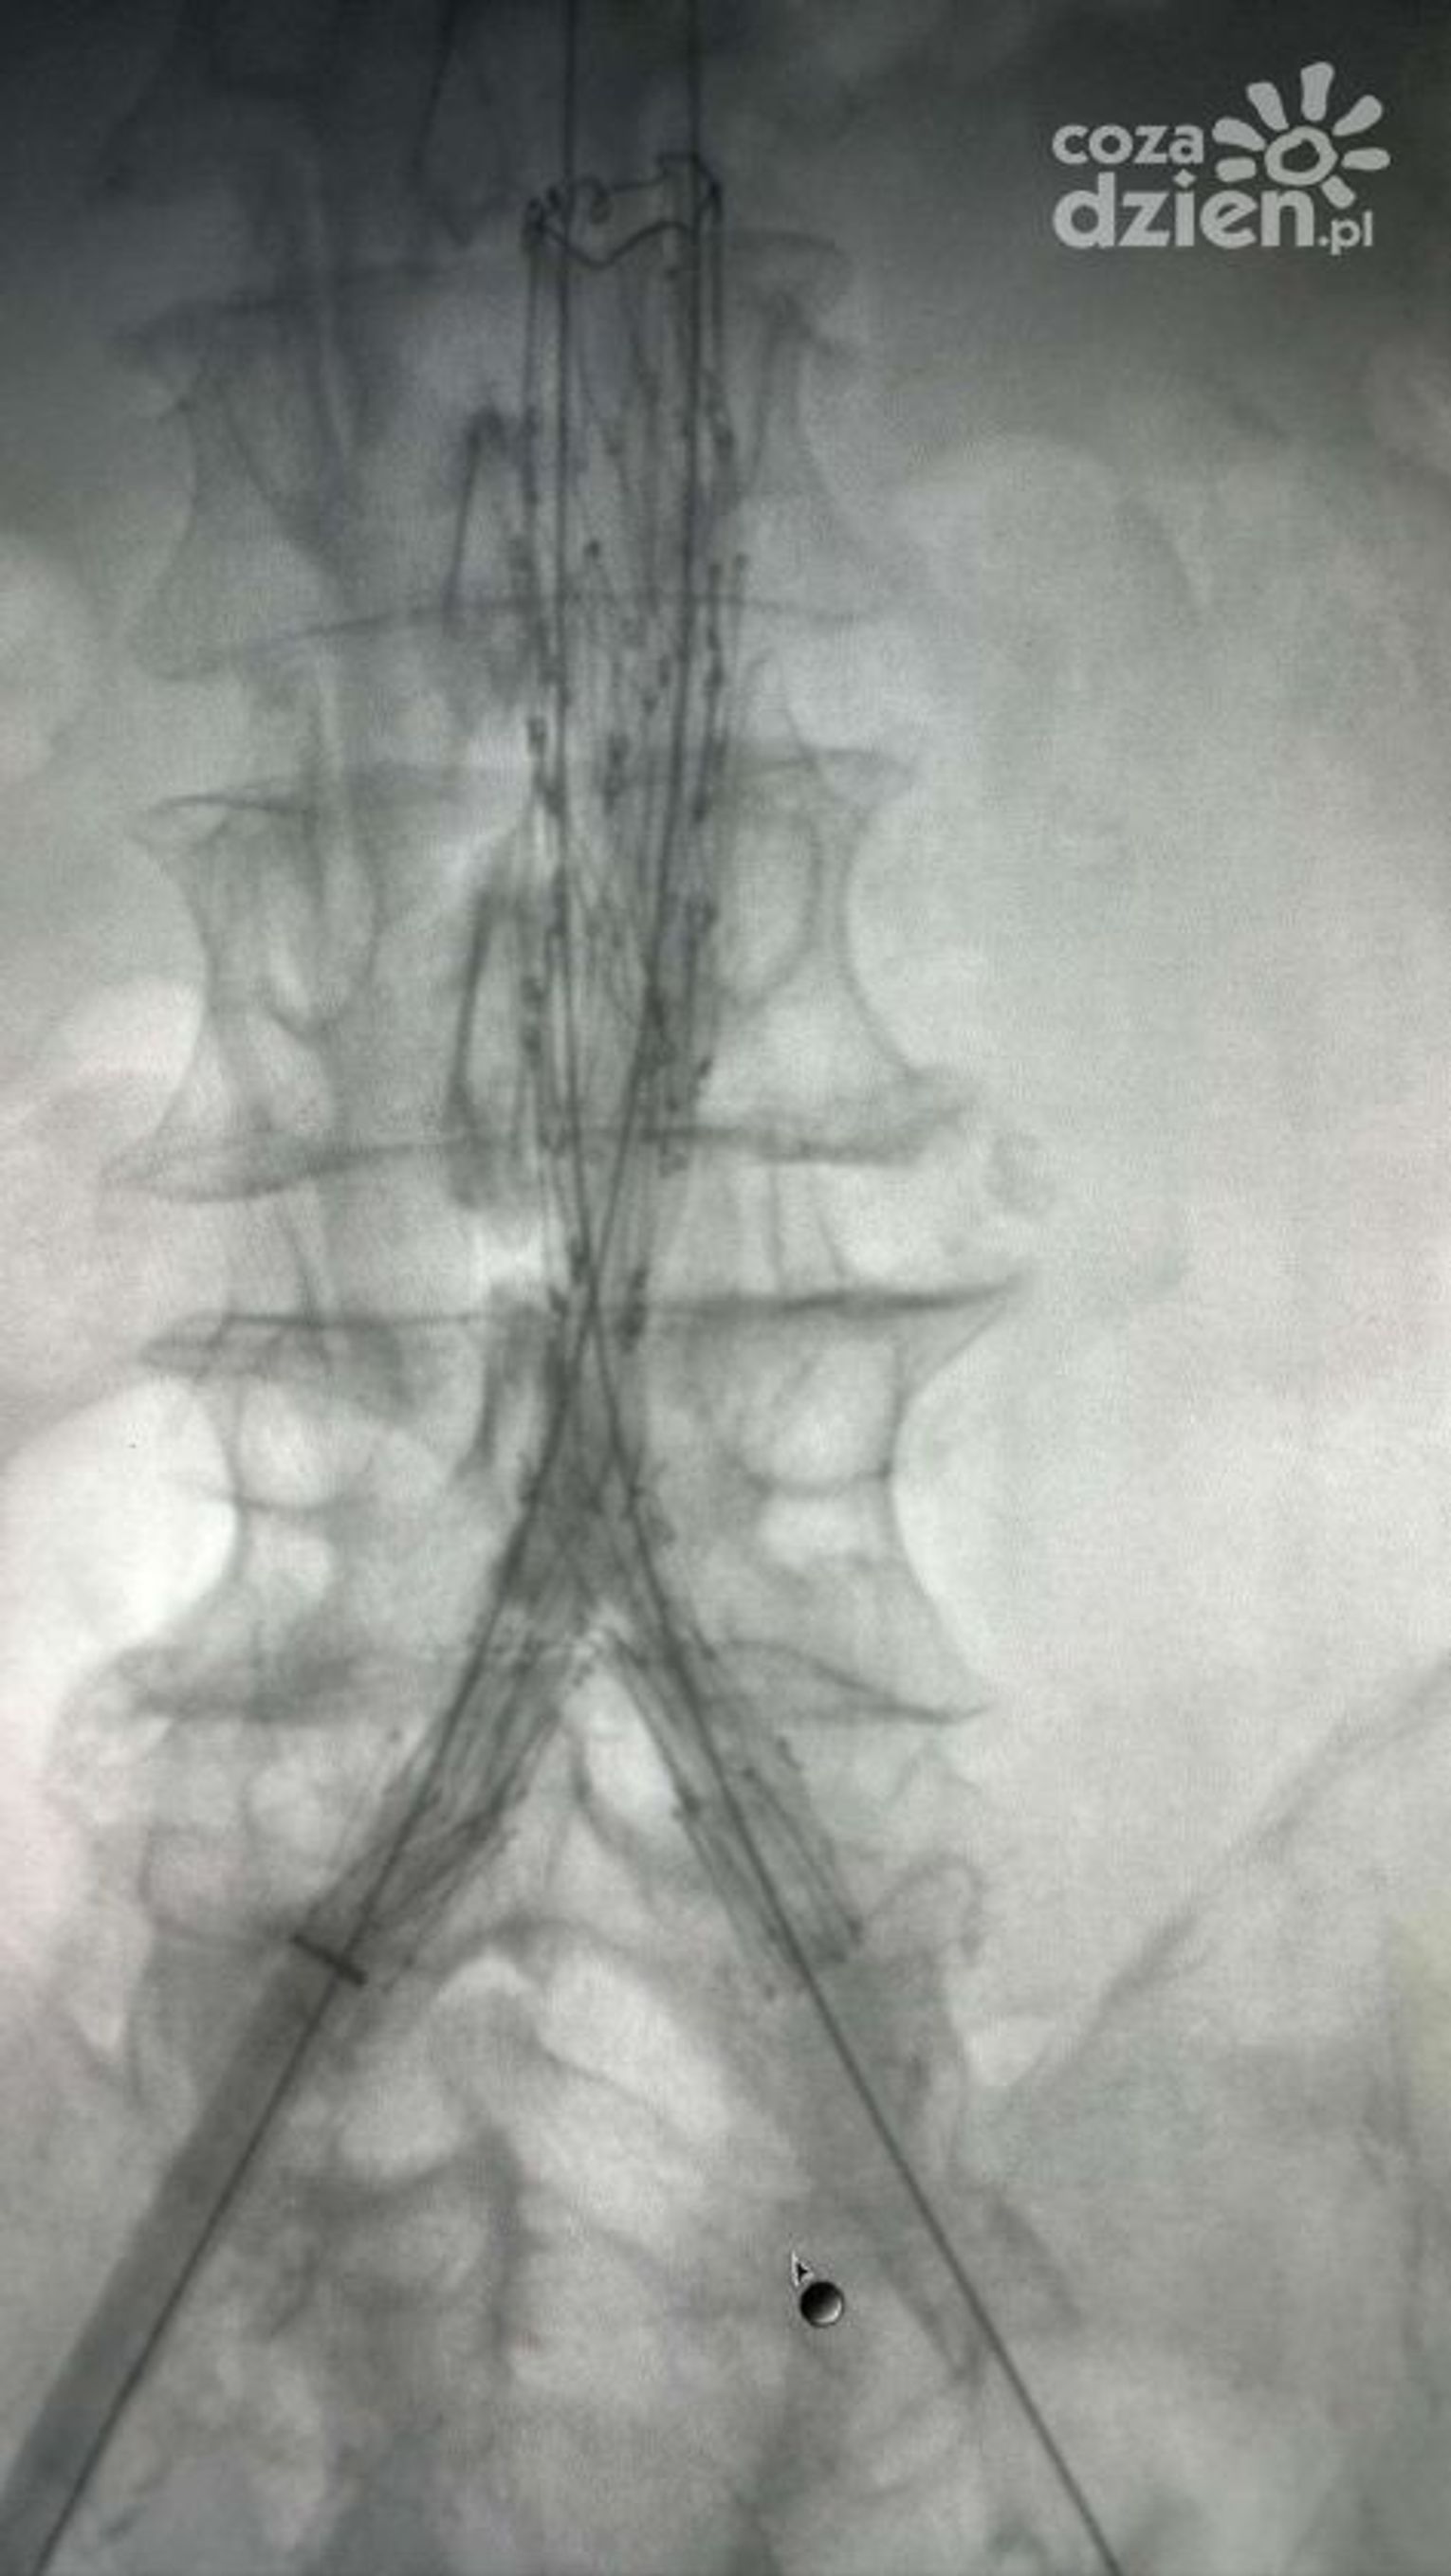

Oddział chirurgii naczyniowej na Józefowie działa zaledwie od kilku miesięcy. Przez ten czas zakres usług szpitala znacznie się poszerzył. Stopniowo wprowadzane są coraz bardziej zaawansowane zabiegi. Przykładem jest przeprowadzona również w ostatnim czasie trzyetapowa operacja tętniaka aorty brzusznej i prawej tętnicy biodrowej. - Powiem pani szczerze, że jestem zachwycony, że tak się czuję po trzeciej już operacji - komentuje Włodzimierz Wiśniewski, pacjent

W obu przypadkach wszystko przebiegło zgodnie z planem, a pacjentów czeka teraz rehabilitacja.